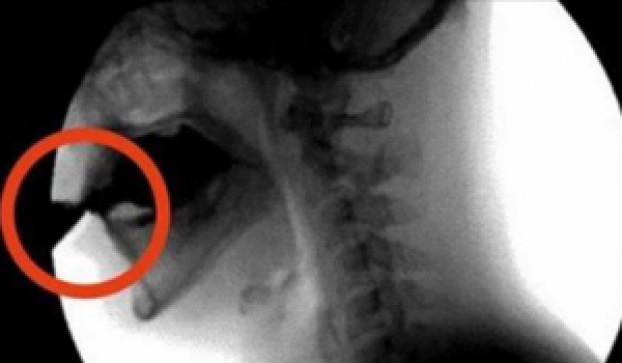

Diuretička svojstva kofeina počinju da djeluju i svi minerali, uključujući magnezijum, kalcijum i cink namenjene kostima, tada se izlučuju u urinu.